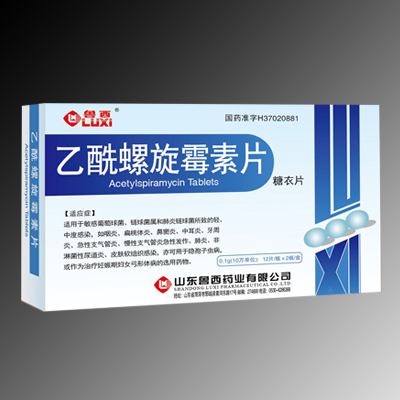

乙酰(xiān)螺旋黴素片

乙酰(xiān)螺旋黴素片 -